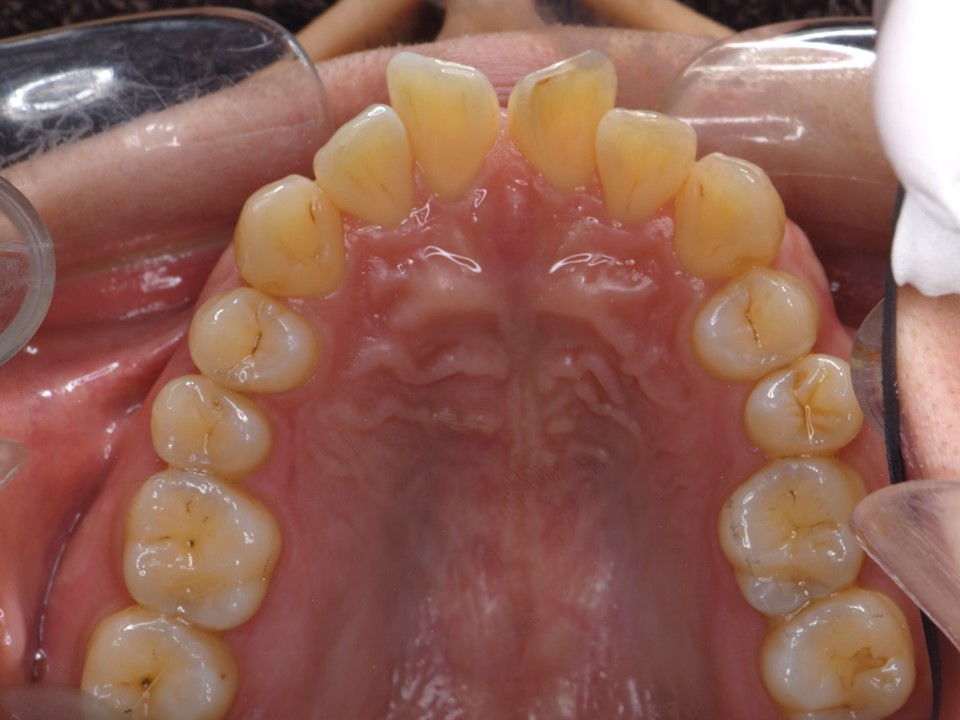

矯正治療前口腔内。歯周病により歯列不正を生じた30代女性。歯周病が進行していたため、全顎的な歯周初期治療および歯周外科処置(フラップ手術)を行った。右側下顎第一大臼歯は保存不可能であったため抜歯となった。上下前歯部は叢生(乱杭歯、クラウディング)を生じ、審美的にも機能的にも問題がある。歯列矯正を行うと、口腔内清掃が難しくなるため、治療前に正しいブラシイングの方法と習慣をきちんと身につけておく必要がある。また虫歯や根尖病巣がある場合には、矯正治療に伴い病状が進行するため、あらかじめ治療を済ませておく。